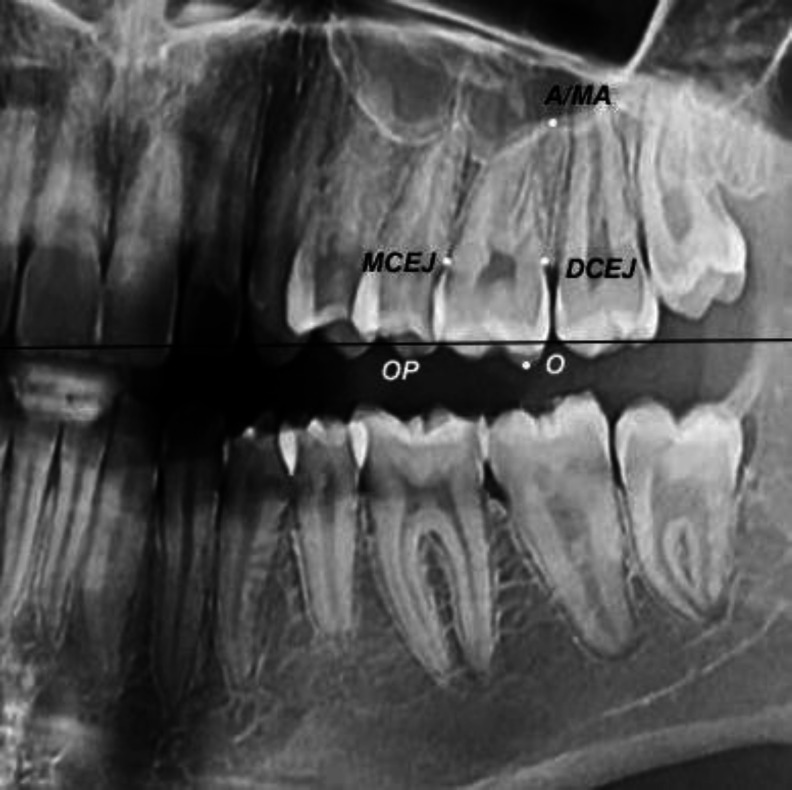

Objectives: This study assessed sex estimation of Iranians according to maxillary left first molar measurements made on panoramic radiographs using classical and machine-learning classifiers. Materials and Methods: In this cross-sectional study, tooth length- and width-related variables were calculated for maxillary left first molars on 131 panoramic radiographs (65 males, 66 females; age range of 18-30 years). A subsample of the radiographs was selected and reevaluated by two examiners after 1 month. The intra-class correlation coefficient (ICC) was calculated to assess reliability. The regularized discriminant analysis (RDA), support vector machine (SVM), and cascade-forward and feed-forward neural network models were used for sex estimation. Comparisons were made with the Mann-Whitney and t tests. Results: The intra-observer reliability was 0.9. SVM had the best performance on the test data in both classification schemes. The crown length at the cementoenamel junction (CEJL) and total crown length (CL) in the classification scheme I (sex estimation based on length and width variables), and CEJL/root length (RL), cementoenamel junction width (CEJW)/CEJL, and RL/total tooth length (TTL) in the classification scheme II (sex estimation based on the ratio of variables) were important variables for sex estimation determined by the SVM model. The CEJL had the highest discriminative potential with an area under the curve (AUC) of 78.8. The ratio of variables did not substantially improve sex estimation compared with single variables. Conclusion: CEJL is a reliable measure for sex estimation in Iranians with values higher than 6.25 indicating the male sex and other values indicating the female sex.